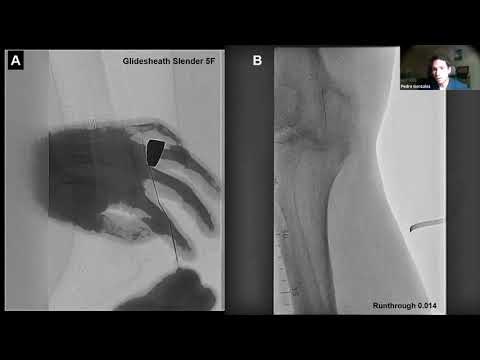

Advanced Techniques to Cross Complicated and Calcified Femoropopliteal CTOs